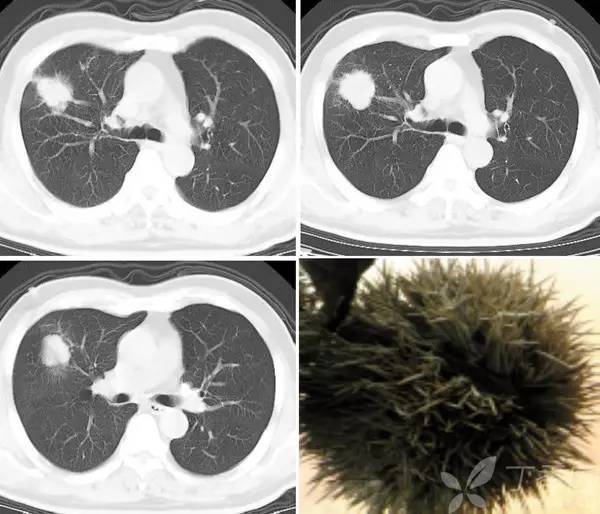

在平片或 CT 肺窗上常常可以看到自肺内肿块或结节边缘向肺周围实质伸展的、不与胸膜相连的放射状无分支短线状影。

小于 5 mm 的毛刺称为短毛刺,大于或等于 5 mm 的称为长毛刺。肺结节或肿块边缘有很多种情况,锯齿、尖角、三角形、分叶等,其中前三种情况称作棘突征;边缘线条影如果和胸膜相连则称作胸膜凹陷征;如果边缘线条有分支,则为血管影。

毛刺征主要见于周围型肺癌,是肿瘤细胞向邻近血管鞘或局部淋巴结浸润,或者促结缔组织生成反应形成的纤维带。良性结节如炎性假瘤和结核球,边缘也可见毛刺,不过常常是长毛刺。